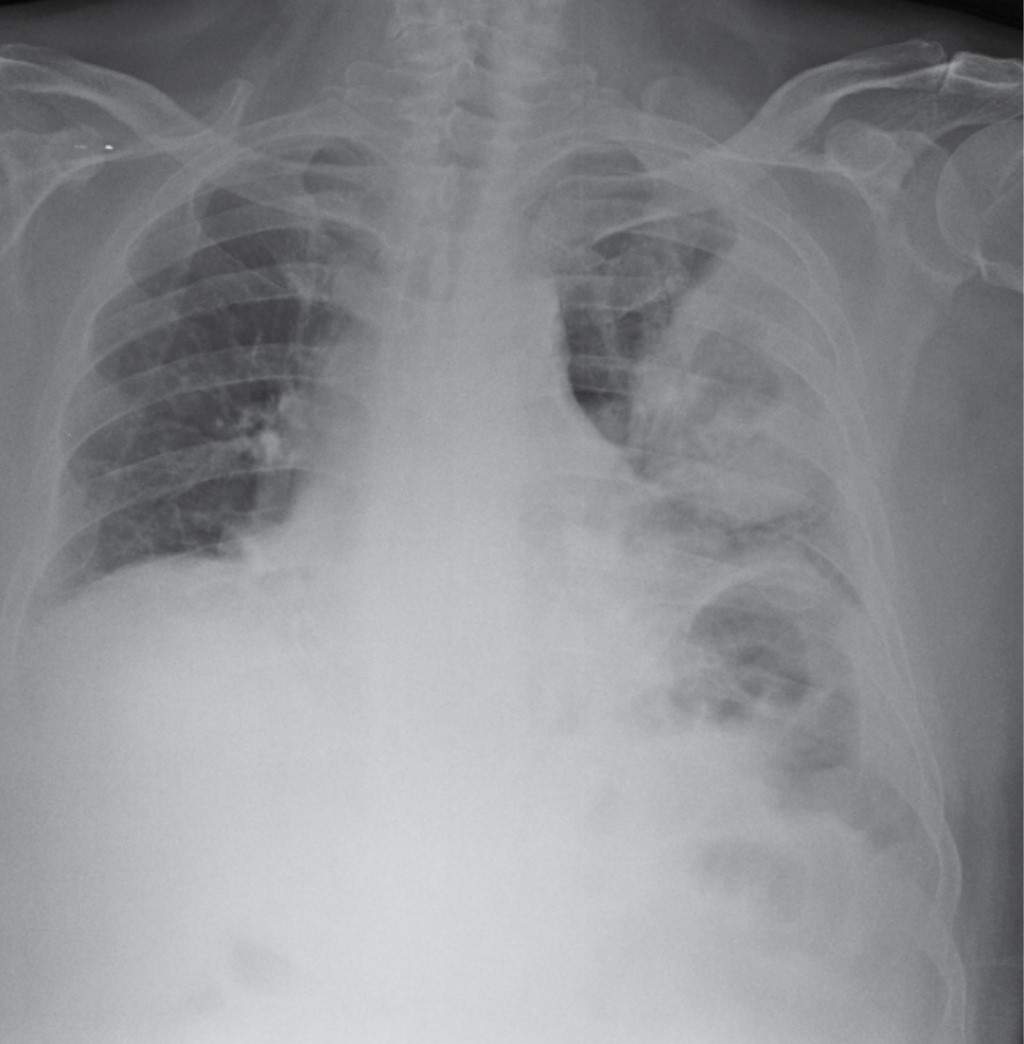

Hombre de 68 años de edad, el cual acude a nuestro hospital en julio 2023 por presentar tos no productiva con expectoración blanquecina, acompañada de disnea de medianos esfuerzos; niega fiebre, sufre pérdida de peso de 6 kg en las últimas semanas. Después de recibir tratamiento antiinfeccioso en el departamento de urgencias durante dos días, con poca mejoría, ingresó a neumología para protocolo diagnóstico y terapéutico; se tomó radiografía de tórax al momento de su ingreso (Figura 1); se programó estudio tomográfico de tórax (Figura 2), donde se encontró masa cavitada bien definida dentro del lóbulo superior izquierdo, con el signo de la media luna de aire. Por sospecha diagnóstica de tuberculosis pulmonar, se solicitó estudio de broncoscopia para lavado broncoalveolar y prueba de bacilos ácido-alcohol resistentes (BAAR), cultivo de micobacterias y de hongos, así como de bacterias. Durante el estudio con fibrobroncoscopia se observó una masa exofítica blanquecina en la pared anterior segmento S3 izquierdo, por lo que se decidió toma de biopsia y de muestras (Figura 3); posteriormente, mediante estudio histopatológico, se realizó el diagnóstico de mucormicosis y, por cultivo, mucormicosis Absidia. Se inició manejo con anfotericina B; durante los primeros tres días de iniciado el tratamiento, el paciente aumenta requerimiento de oxígeno, se solicita nueva radiografía de tórax; llega a mascarilla reservorio 15 litros con saturación de 90% con taquipnea, frecuencia respiratoria 30 por minuto, con disociación toracoabdominal, por lo que se decide manejo avanzado de la vía aérea. Fallece por choque séptico en sus primeras 12 horas de estancia en terapia intensiva respiratoria.

Las manifestaciones radiológicas de la mucormicosis pulmonar son en su mayoría inespecíficas; más del 80% de los pacientes muestran resultados anormales en las radiografías de tórax.11 Los hallazgos pueden incluir consolidación, cavitación, el signo de la media luna de aire, el signo del halo, el signo del halo invertido, nódulos o masas pulmonares múltiples o solitarias, fístulas broncopleurales, pseudoaneurismas de la arteria pulmonar, linfadenopatía y derrame pleural. La cavitación se observa en hasta 40% de los casos, aunque el signo de la media luna de aire es poco común. La tomografía computarizada (TC) de alta resolución puede ser más sensible para detectar la enfermedad y puede encontrar evidencia de la infección antes que las radiografías de tórax convencionales. El pulmón derecho se ve afectado con mayor frecuencia que el izquierdo, y hay una predilección por la afectación de los lóbulos superiores, aunque la razón detrás de esto se desconoce. El presente caso reportó una lesión en el lóbulo superior derecho, al igual que la mayoría de los casos en la literatura.11